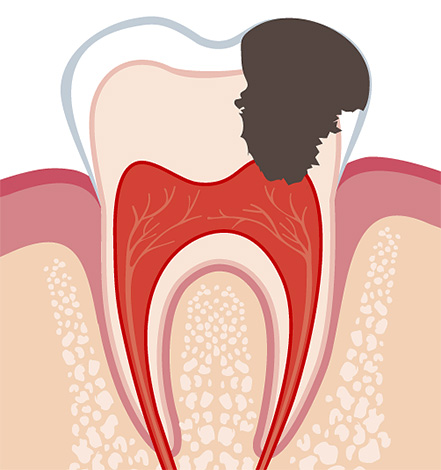

In generale, la pulpite è un'infiammazione del fascio neurovascolare all'interno della corona del dente e dei canali radicolari. Se in alcuni casi di polmonite acuta (focale) è possibile interrompere il processo infiammatorio e trattare il dente in modo conservativo, cioè senza rimozione del nervo, quindi la pulite cronica è quasi sempre una forma irreversibile della malattia. In questo caso, una graduale degenerazione della polpa avviene all'interno del dente: la formazione di tessuto fibroso, la necrosi (necrosi) o la proliferazione del fascio neurovascolare fino a riempire la cavità che porta alla patologia.

Poiché la pulpite cronica è una forma irreversibile di infiammazione dei tessuti molli, quando non possono più essere immagazzinati nel dente, vengono spesso utilizzati per il trattamento estrazione completa della polpa da tutti i canali dentali. Lo stesso approccio è seguito nel trattamento della pulpite cronica nella fase acuta.

Nell'odontoiatria moderna, viene data preferenza al metodo di estirpazione (estrazione) vitale del "nervo". Durante il trattamento delle forme croniche di pulpite o delle sue esacerbazioni, viene utilizzata solo l'anestesia senza fondi aggiuntivi per la devitalizzazione (uccisione) della polpa.